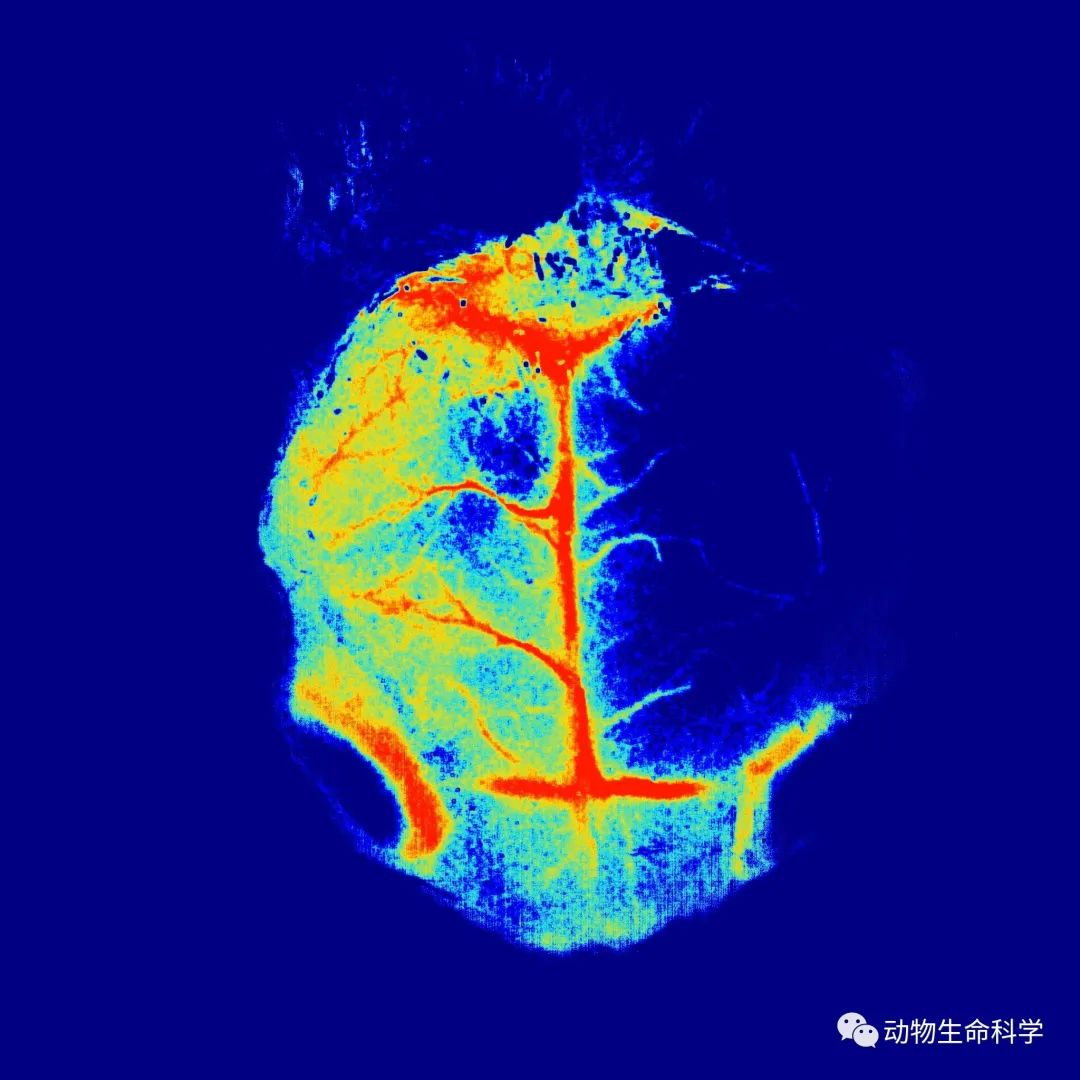

(7) 手术结束后应用激光散斑血流成像系统监测大脑皮层血流,当看到大脑皮层血液血流降低70%~80%,说明模型制备成功。

(2)采用散斑血流仪,实时观测颅脑血流情况。这样可以准确判断线栓是否阻塞MCA,一旦血流灌注量下降超过70%,即代表线栓阻塞MCA。

(3)MCAO线栓手术属于显微操作手术,不可控因素较多,需要多练习。一般常规连续练习3个月左右,即可实现造模;如果采用血流仪辅助造模,时间可以缩短至1个月,手术过程中可以实时调整线栓位置。另外现在发文越来越需要漂亮数据,瑞沃德的激光散斑血流仪RFLSI Ⅲ可提供高清漂亮血管血流分布图。

瑞沃德激光散斑血流成像系统RFLSI Ⅲ